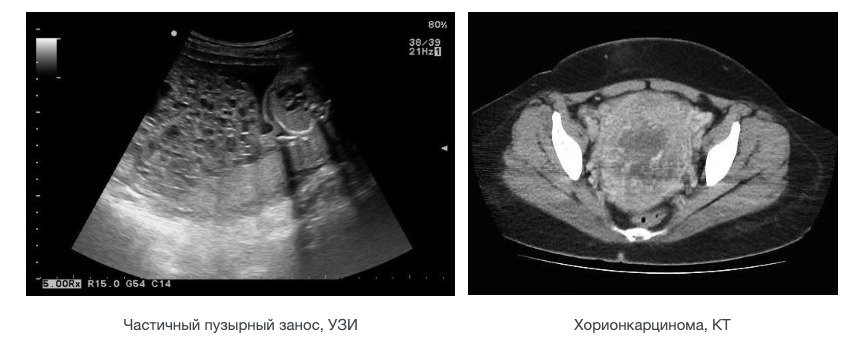

- УЗИ органов малого таза – для первичного подтверждения болезни;

- МРТ органов малого таза – для уточнения расположения опухоли;

- КТ органов грудной клетки, брюшной полости, МРТ головного мозга — для поиска метастазов;

- частичный пузырный занос. Образуется при оплодотворении яйцеклетки сразу двумя сперматозоидами. Такой эмбрион содержит дополнительный набор хромосом, и, к сожалению, является нежизнеспособным;

Эти доброкачественные опухоли диагностируются у 70 % больных, при этом как при полном, так и неполном пузырном заносе наблюдается только разрастание трофобластической ткани и превращение ворсинок хориона в пузырьки. Однако в 20 % случаев трофобласты приобретают способность к малигнизации и метастазированию. По мере распространения злокачественных клеток в окружающие ткани различают инвазивный пузырный занос, диссеминированный пузырный занос, хорионкарционому, трофобластическую опухоль плацентарного ложа и эпителиоидную трофобластическую опухоль.